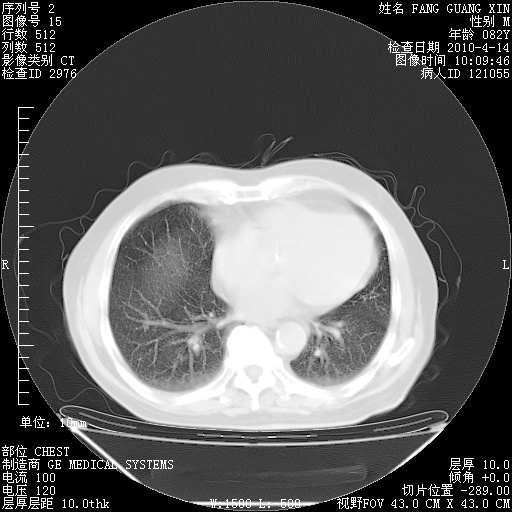

肺部CT平扫未见异常。

4月14日肺部CT